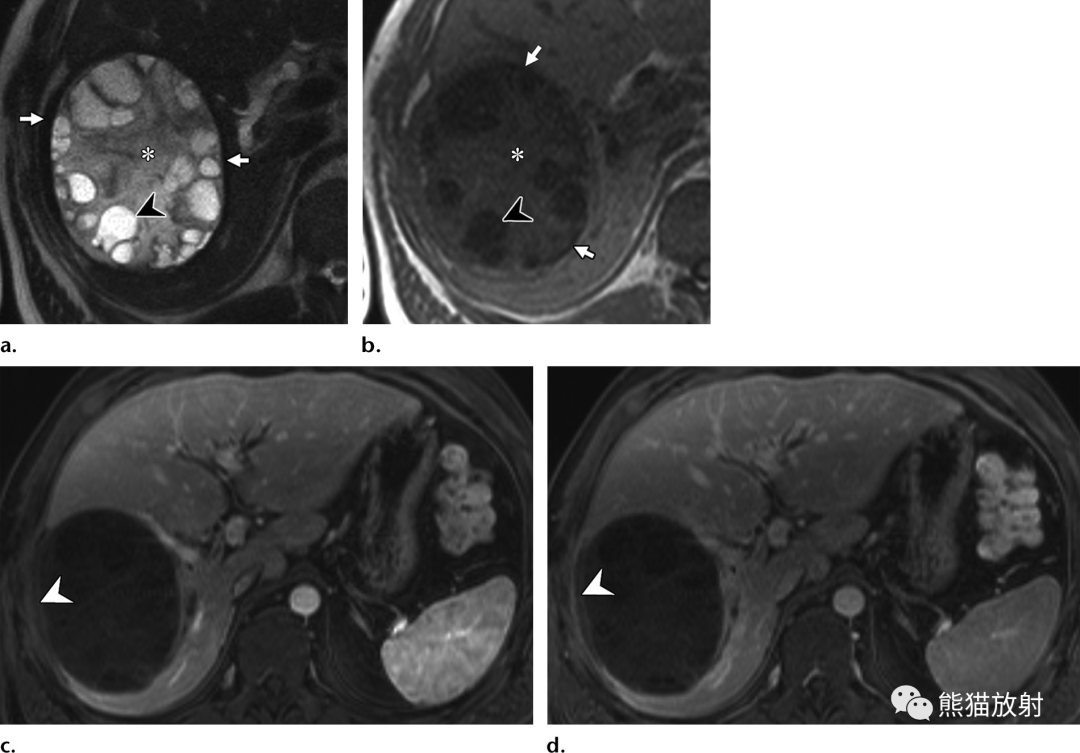

37岁智利男性患者,肝包虫病,表现为右肋下疼痛。(a)T2WI显示囊外周呈明显低信号边缘,由于其纤维成分或包膜钙化所致(箭)。棘球蚴基质 (*) 呈中等信号强度。子囊(箭头)如果存在,表明囊肿有活性,其相对于底层基质为T2高信号。(b)T1WI同相位显示低信号的纤维囊壁(箭)。棘球蚴基质 (*)呈等信号。子囊(箭头)相对于包虫基质呈低信号。(c,d)对比增强脂肪抑制门脉期(c) 和延迟期(d) 图像显示囊肿内容物无强化,外周囊壁(箭头)轻度强化。